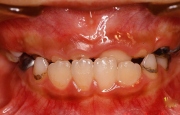

早期治療

早期治療後